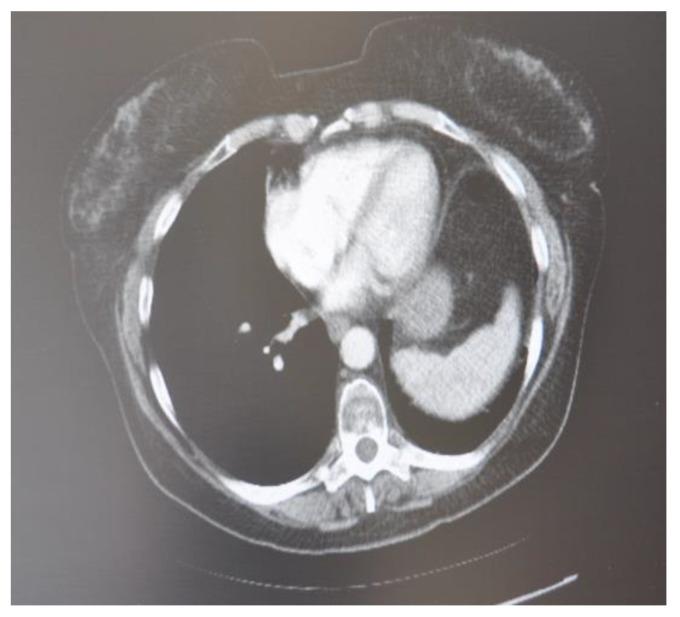

As less invasive options for surgical tumor removal, minimally invasive ablative techniques have gained popularity. Several solid tumors are being treated with cryoablation, a non-heat-based ablation technique. Cryoablation data in comparison over time demonstrates better tumor response and faster recovery. Combining cryosurgery with other cancer therapies has been explored to improve the cancer-killing process. Cryoablation with the combination of immunotherapy, results in a robust and efficient attack on the cancer cells. This article focuses on investigating the ability of cryosurgery to create a strong antitumor response when combined with immunologic agents resulting in a synergetic effect. To achieve this objective, we combined cryosurgery with immunotherapy using Nivolumab and lpilimumab. Five clinical cases of lymph node, lung cancer, bone, and lung metastasis were followed and analyzed. In this series of patients, percutaneous cryoablation and addressing immunity agents were technically feasible. In the follow-ups, there appeared to be no radiological evidence of new tumor development.

作为手术肿瘤切除的微创选择,微创消融技术已经越来越受欢迎。几种实体肿瘤正在接受冷冻消融治疗,这是一种非热消融技术。随着时间的推移,冷冻消融的数据显示出更好的肿瘤反应和更快的恢复。冷冻手术与其他癌症治疗方法的结合已被探索用于改善癌症杀伤过程。冷冻消融联合免疫疗法可以有效地攻击癌细胞。本文重点研究了冷冻手术与免疫药物联合使用时对肿瘤产生强烈抗肿瘤反应的能力,从而产生协同作用。为了实现这一目标,我们使用 Nivolumab 和 ipilimumab 将冷冻手术与免疫疗法相结合。对 5 例淋巴结、肺癌、骨和肺转移的临床病例进行了随访和分析。在这一系列患者中,经皮冷冻消融和免疫治疗具有技术可行性。在随访中,似乎没有新的肿瘤发展的放射学证据。